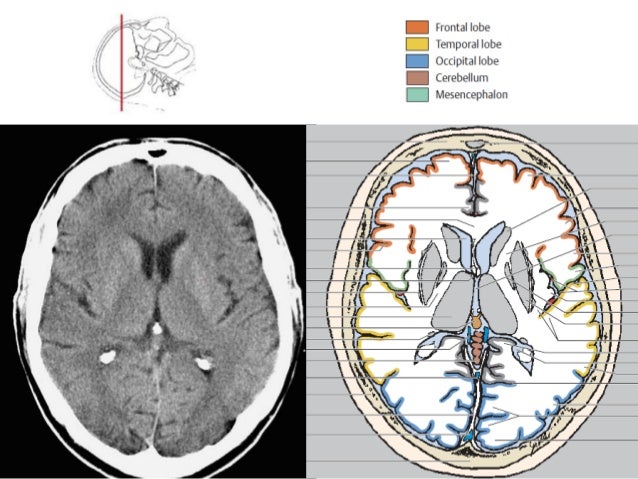

BASICS of CT Head

Basic approach to brain CT Dr. Muhammad Bin Zulfiqar